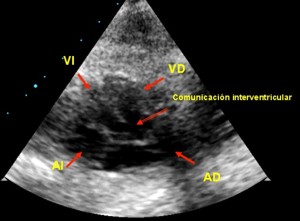

La comunicación interventricular (CIV) es visible en el corte de cuatro cámaras si su situación es posterior, y en el cinco cámaras si su posición es anterior o infundibular, como ocurre en el Fallot.

Comunicación interventricular del Fallot

(Ver imagen y video del Fallot en 5 cámaras): El tabique interventricular desaparece debajo de la válvula aórtica, y ambos ventrículos quedan comunicados a su través. Se trata de una CIV subaórtica, típica de algunas cardiopatías complejas como la Tetralogía de Fallot.

Cinco Cámaras, Fallot